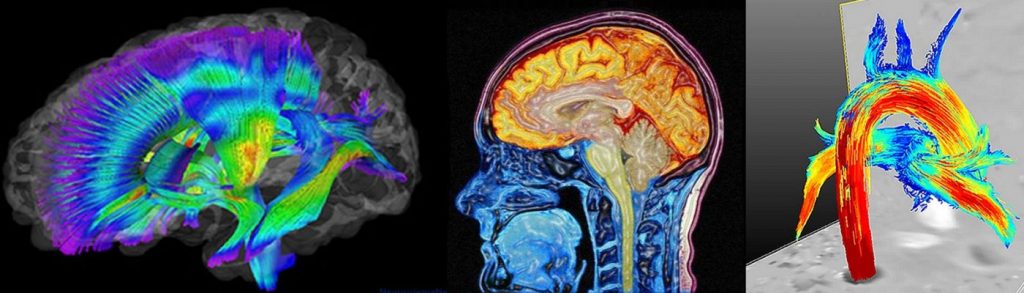

Cerebro

- Evaluar afecciones en el cerebro en pacientes, con algunos síntomas y trastornos tales como convulsiones, pérdida de la memoria y anomalías en el flujo sanguíneo.

- Detectar si aparece de manera temprana, desordenes neurológicos como el Alzheimer.

- Ayuda a planificar una cirugía, para identificar las zonas del cerebro que este causando las convulsiones.

- Evaluar la presencia de enfermedades en una substancia química del cerebro, que se encuentre involucrada en el control del movimiento, en pacientes que puedan padecer Parkinson o desórdenes similares del movimiento.

- Supervisión de la sospecha de frecuentes tumores cerebrales, planeamiento de la radioterapia, cirugía, o ubicación para la biopsia.